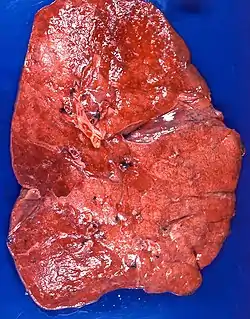

| Lipid pneumonia, exogenous Case 108 | |

Appearance

The gross appearance of a lipid pneumonia is that in which there is an ill-defined, pale yellow area on the lung. This yellow appearance explains the colloquial term "golden" pneumonia.[7]

At the microscopic scale foamy macrophages and giant cells are seen in the airways, and the inflammatory response is visible in the parenchyma.

On CT, lipoid pneumonia appears as a "crazy paving" pattern, characterized by grounglass opacities with interspersed interlobular septal thickening.[8]